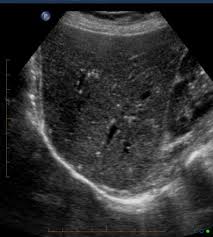

Dark Spots On Kidney Ultrasound

Dark Spots On Kidney Ultrasound. However she said i had a few things in my favor that make that unlikely. They were on either my liver or kidney and there were about 10 varrying in size.

At least â of all spots on kidneys are benign. Chronic kidney disease can also give. I am now awaiting approval for an mri.

No appendicitis but an incidental finding of a spot on my kidney. Most people don t experience any side effects. No appendicitis but an incidental finding of a spot on my kidney. However she said i had a few things in my favor that make that unlikely.